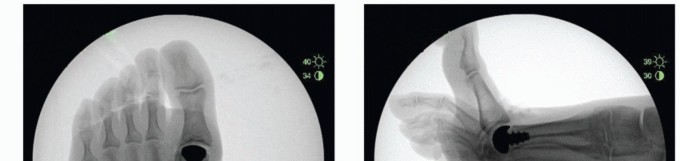

FIG 4 • A. Grade 1 hallux rigidus. B. Grade 2 hallux rigidus. C. Grade 3 hallux rigidus. D. Lateral view of hallux rigidus.

In its early stages, articular cartilage loss is present along the dorsal aspect of the first metatarsal head. As the condition progresses, articular cartilage loss extends to the central aspects of the metatarsal head and lastly the plantar aspect (FIG 2).

FIG 2 • A-C. Varying degrees of articular cartilage loss of the first metatarsal head in hallux rigidus. Radiographic findings often underestimate the extent of disease seen intraoperatively.